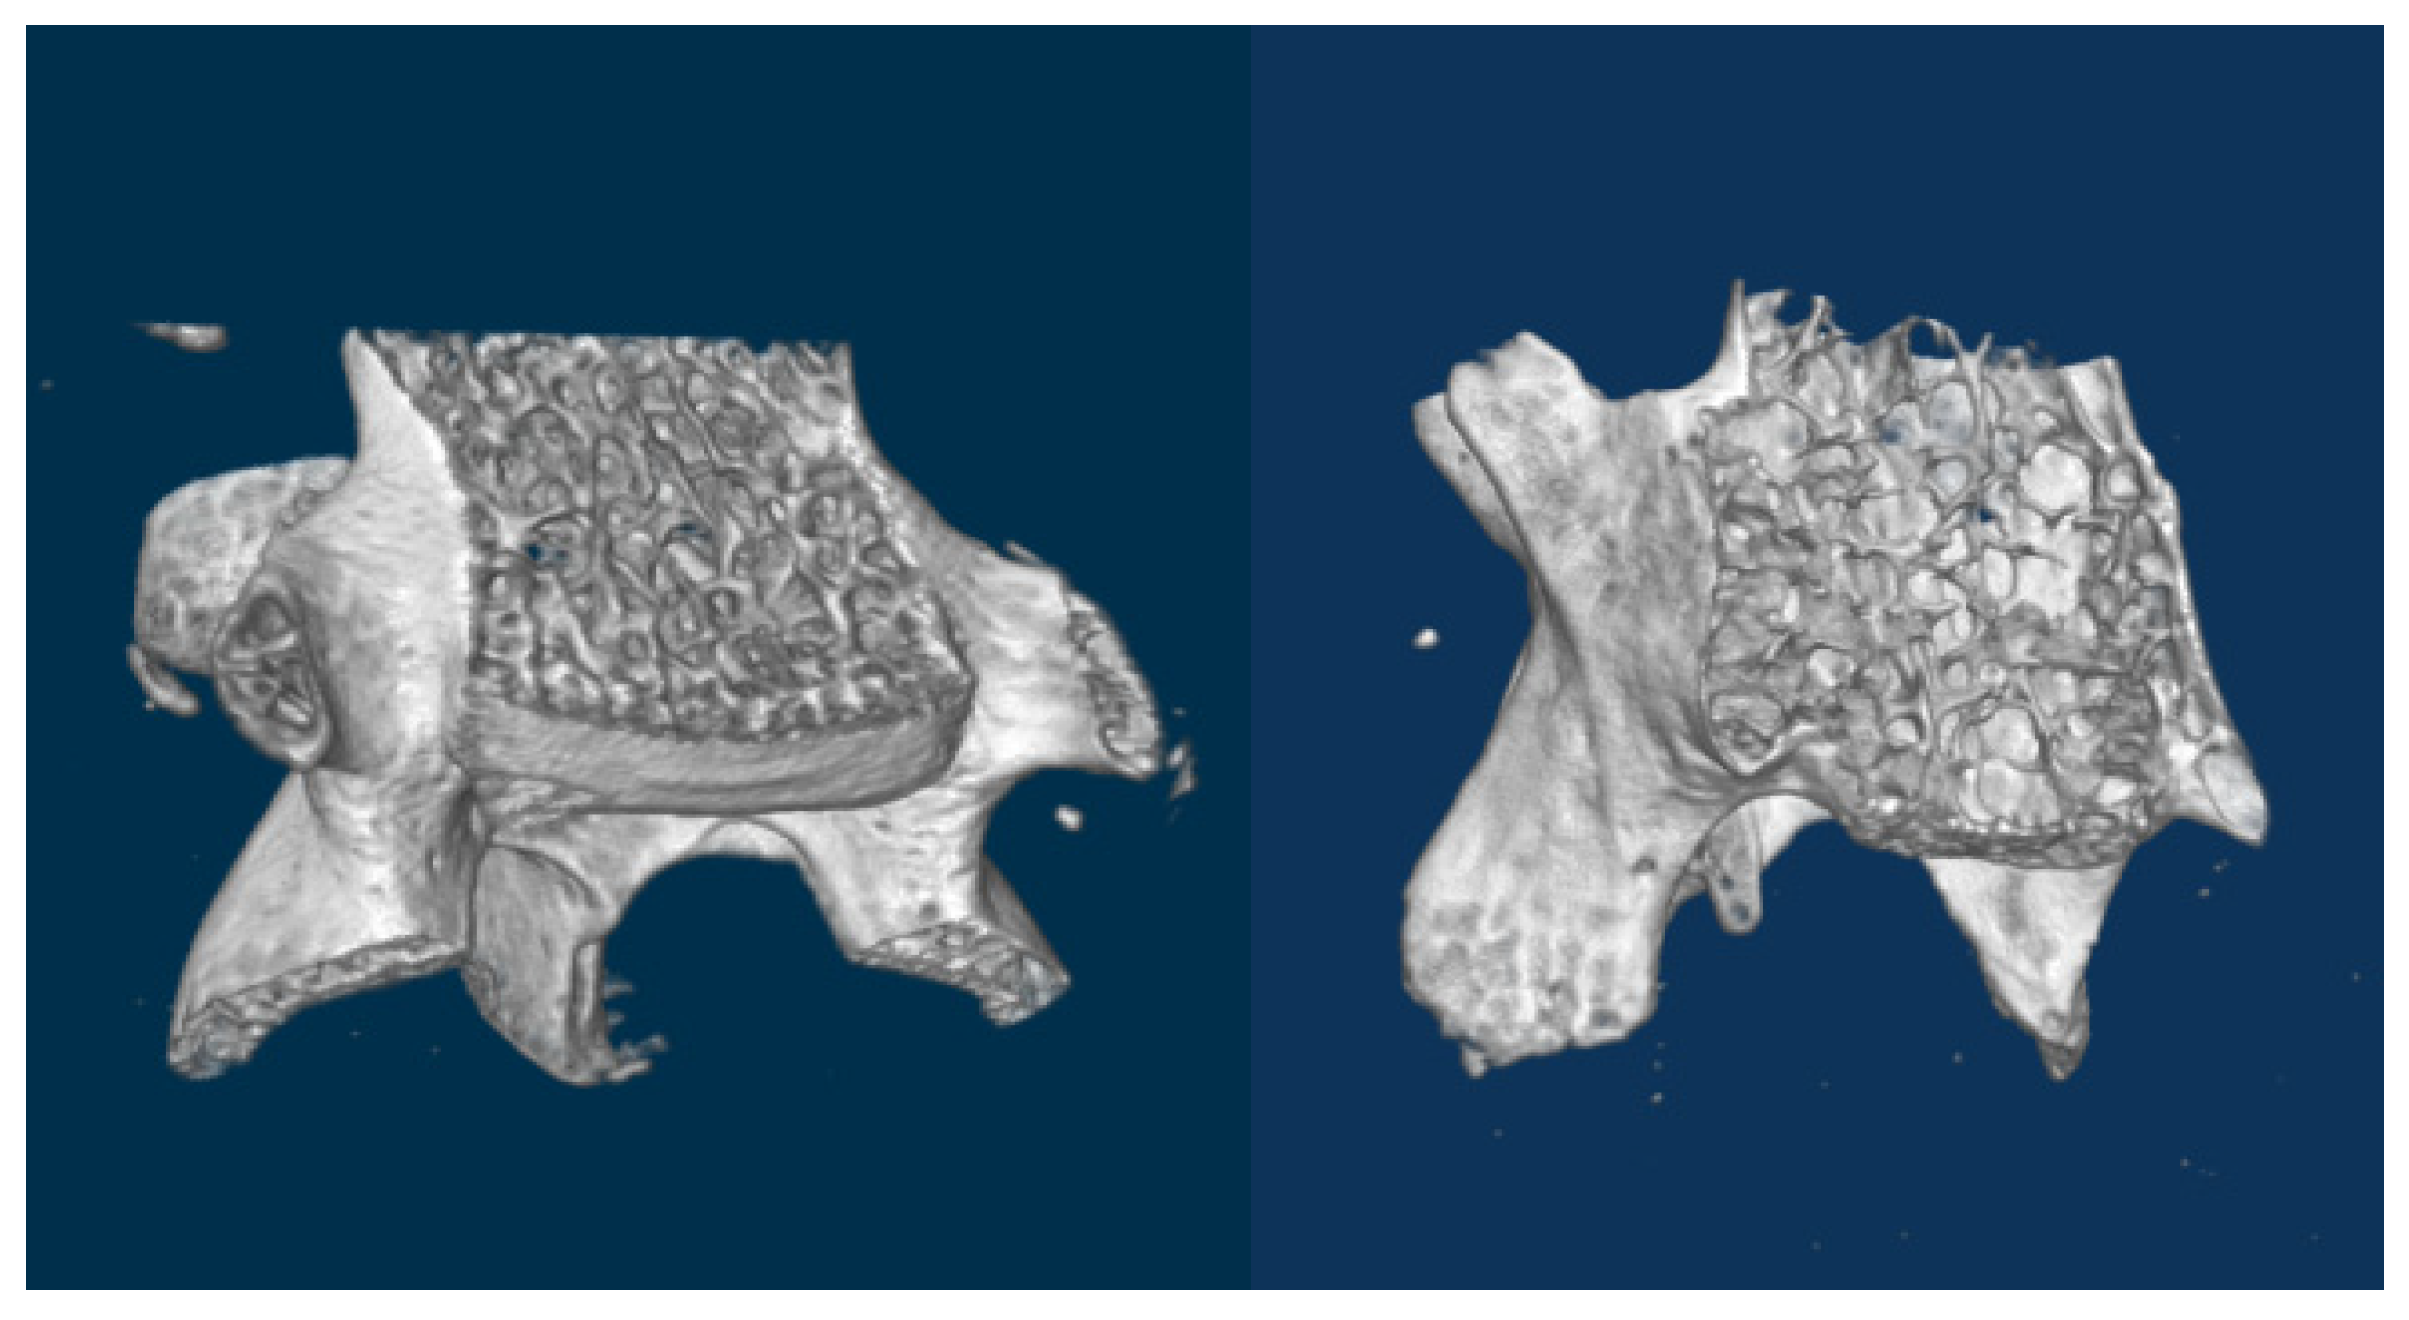

The quality of femur bone, lumbar vertebra, and hip joint of aging mice was evaluated in the present study. Male and female mice of a wide range of ages (7 to 80 weeks), strain Black6, were scanned using X-ray microtomography. Parameters such as mineral density were calculated to assess bone quality.

The parameter values and the images recorded reveal that bony and cartilage tissues remain in healthy condition until the age of 1 year. From this point, decay takes place in bone (osteoporosis) and joints (osteoarthritis). Mineral density of femur and vertebra trabecular bone decreases, while the free space between bone rods increases. The spongy architecture is maintained with wider gaps. The trabecular bone becomes less (Figure 1).

The cartilage covering the femoral head in hip joints mineralizes. It converts to a thick bony layer, losing the elastic properties of the chondral tissue (Figure 2). Osteoarthritis is installed. On the other hand, subchondral bone remains dense until the age of 80 weeks.

Figure 2.

(Left): 7 weeks (healthy) femoral head section. Outer cartilagenous layer is evident. (Right): 80 weeks (osteoarthritic) femoral head section. Cartilage has completely mineralized.